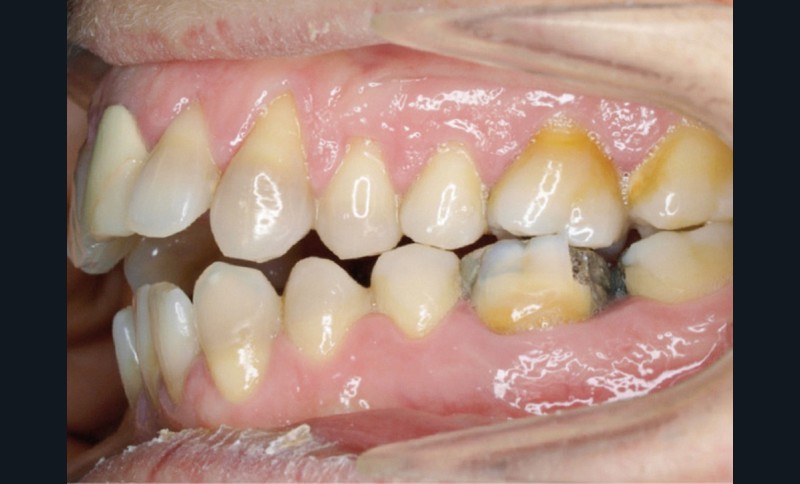

En 2008, la patiente, âgée de 34 ans, se présente pour le traitement de ses « dents mal placées, et de l’écart entre les dents du haut et du bas » (fig. 1). Elle a déjà bénéficié d’un traitement adolescent par plaque amovible maxillaire.

Au niveau exobuccal, la patiente présente un visage convexe avec un étage inférieur de la face augmenté et une absence de contact bilabial au repos traduisant un contexte dysfonctionnel. Le sourire est gingival et étroit.

L’analyse endobuccale et l’étude céphalométrique (fig. 2, tableau 1) confirment le diagnostic de classe II squelettique hyperdivergente avec une classe II molaire et canine bilatérale, associée à un encombrement, à une dysharmonie du sens transversal par endoalvéolie maxillaire, et une béance antérieure par infra-alvéolie incisive maxillaire dans un contexte dysfonctionnel de la musculature péri-labiale et mentonnière.